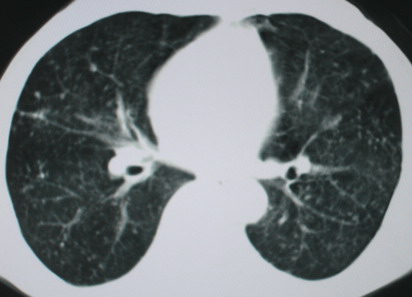

以下是引用医影拾贝在2008-6-3 18:48:00的发言:[br]双上肺弥漫性小结节影,纵隔窗内钙化淋巴结影,考虑血播性tb可能性较大,不除外肺ca可能

以下是引用卜一在2008-6-3 19:33:00的发言:[br]双肺结节,以双上肺分布为多,期间搀杂片状致密影及索条致密影。考虑:继发性肺结核伴血型播散可能性大。不除外肺泡ca的可能!另:椎体退变!

以下是引用panyishengct在2008-6-3 21:09:00的发言:[br]双上肺弥漫性小结节影,纵隔窗内钙化淋巴结影,考虑矽肺或/和tb可能性较大,不除外肺ca可能。腰椎考虑退变。 [br][br]